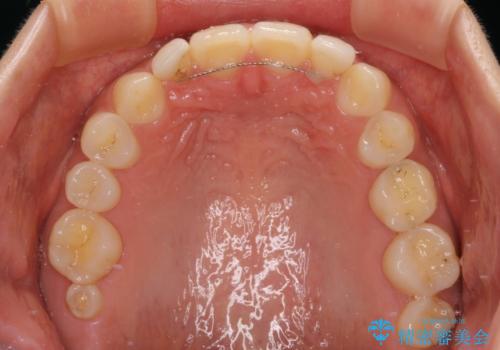

- ラミネートベニアと歯の境目の着色を気にして来院された患者様です。

矯正治療後に矮小歯であった歯をラミネートベニアにて形を変えたそうですが、矯正歯科治療直後であったためか、歯肉の位置が変わったことで境目が見えていました。

着色の原因として、湿気の多い環境で接着操作を行うと、境目に細かいギャップができてしまうことが考えられます。